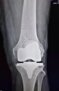

La protesi di ginocchio consiste in un rivestimento completo o parziale dell'articolazione, quindi ricoprendo sia la superficie articolare della tibia che quella del femore. A discrezione del chirurgo ed in base al caso specifico si può rivestire anche la rotula. Volendo semplificare la procedura di impianto di una protesi di ginocchio si possono individuare alcuni passaggi dell'intervento:- preparazione delle superfici ( si asportano i residui di cartilagine, esponendo l'osso sub-condrale in modo da avere una base di appoggio uniforme per la protesi )

-impianto delle componenti metalliche ( si impiantano due componenti metalliche articolari una per il femore e l'altra per la tibia, che costituiranno la nuova articolazione )

-posizionamento dell'inserto ( tra le due componenti metalliche del femore e della tibia viene posizionato un inserto in polietilene cioè una plastica ad alto peso molecolare, per curare la superficie di scorrimento ed ammortizzare i carichi, per sostituire la funzione dei menischi, l'inserto può essere fisso oppure mobile attorno ad un perno centrale )

-impianto della rotula ( si può decidere o meno in base al caso specifico se impiantare la protesi della rotula a seconda delle condizioni della cartilagine e della sintomatologia del paziente )

Intervento sicuro, elimina il dolore e corregge eventuali deformità della gamba. Dopo questo intervento potrai riprendere la tua vita di sempre e le normali attività senza dolore.